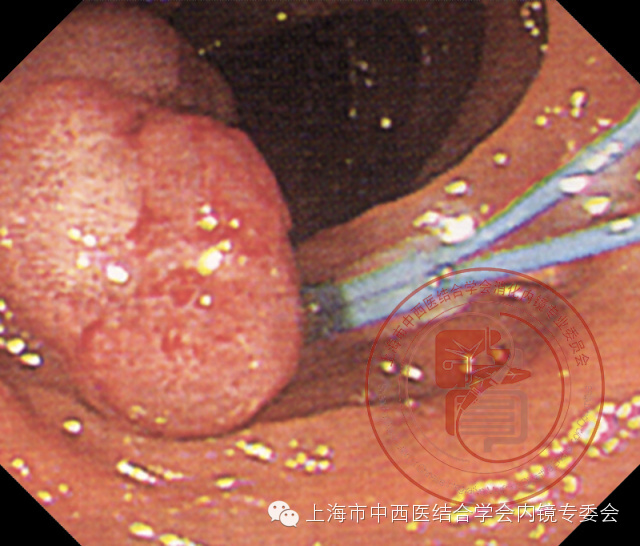

亚蒂息肉

套扎息肉基部